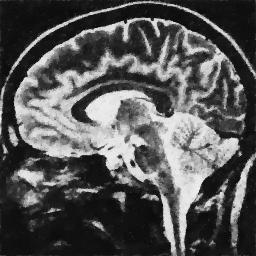

4.1. Uniform Gaussian noise

In this first experiment, we consider the denoising problem with brain scan images. The first set consists of images of pixels and Gaussian noise with zero mean and variance . The original and noisy images are shown in Figure 4.1. The domain decomposition-semismooth Newton algorithms run with the parameter values , , and . The results are shown in Figure 4.2. From the surface representation of , we can observe that is continuous and its shape is related to the one of the original image. In particular, the regularization is stronger in homogeneous regions in the image, and weaker where the image intensity undergoes variations on a smaller scale.

In Table 4.1 the performance of the different methods is compared. For all of them, only the first 2 domain decomposition iterations were considered. The total number of SSN iterations differ at most by one. The impact of the domain decomposition method becomes clear when comparing the computing times of the methods, corresponding to one, two and four subdomains. The computing time is significantly reduced. The effect of the optimized transmission conditions can be realized when comparing the gap between subdomains, which is much lower in the case of optimized transmission conditions () than in the standard Schwarz method ().